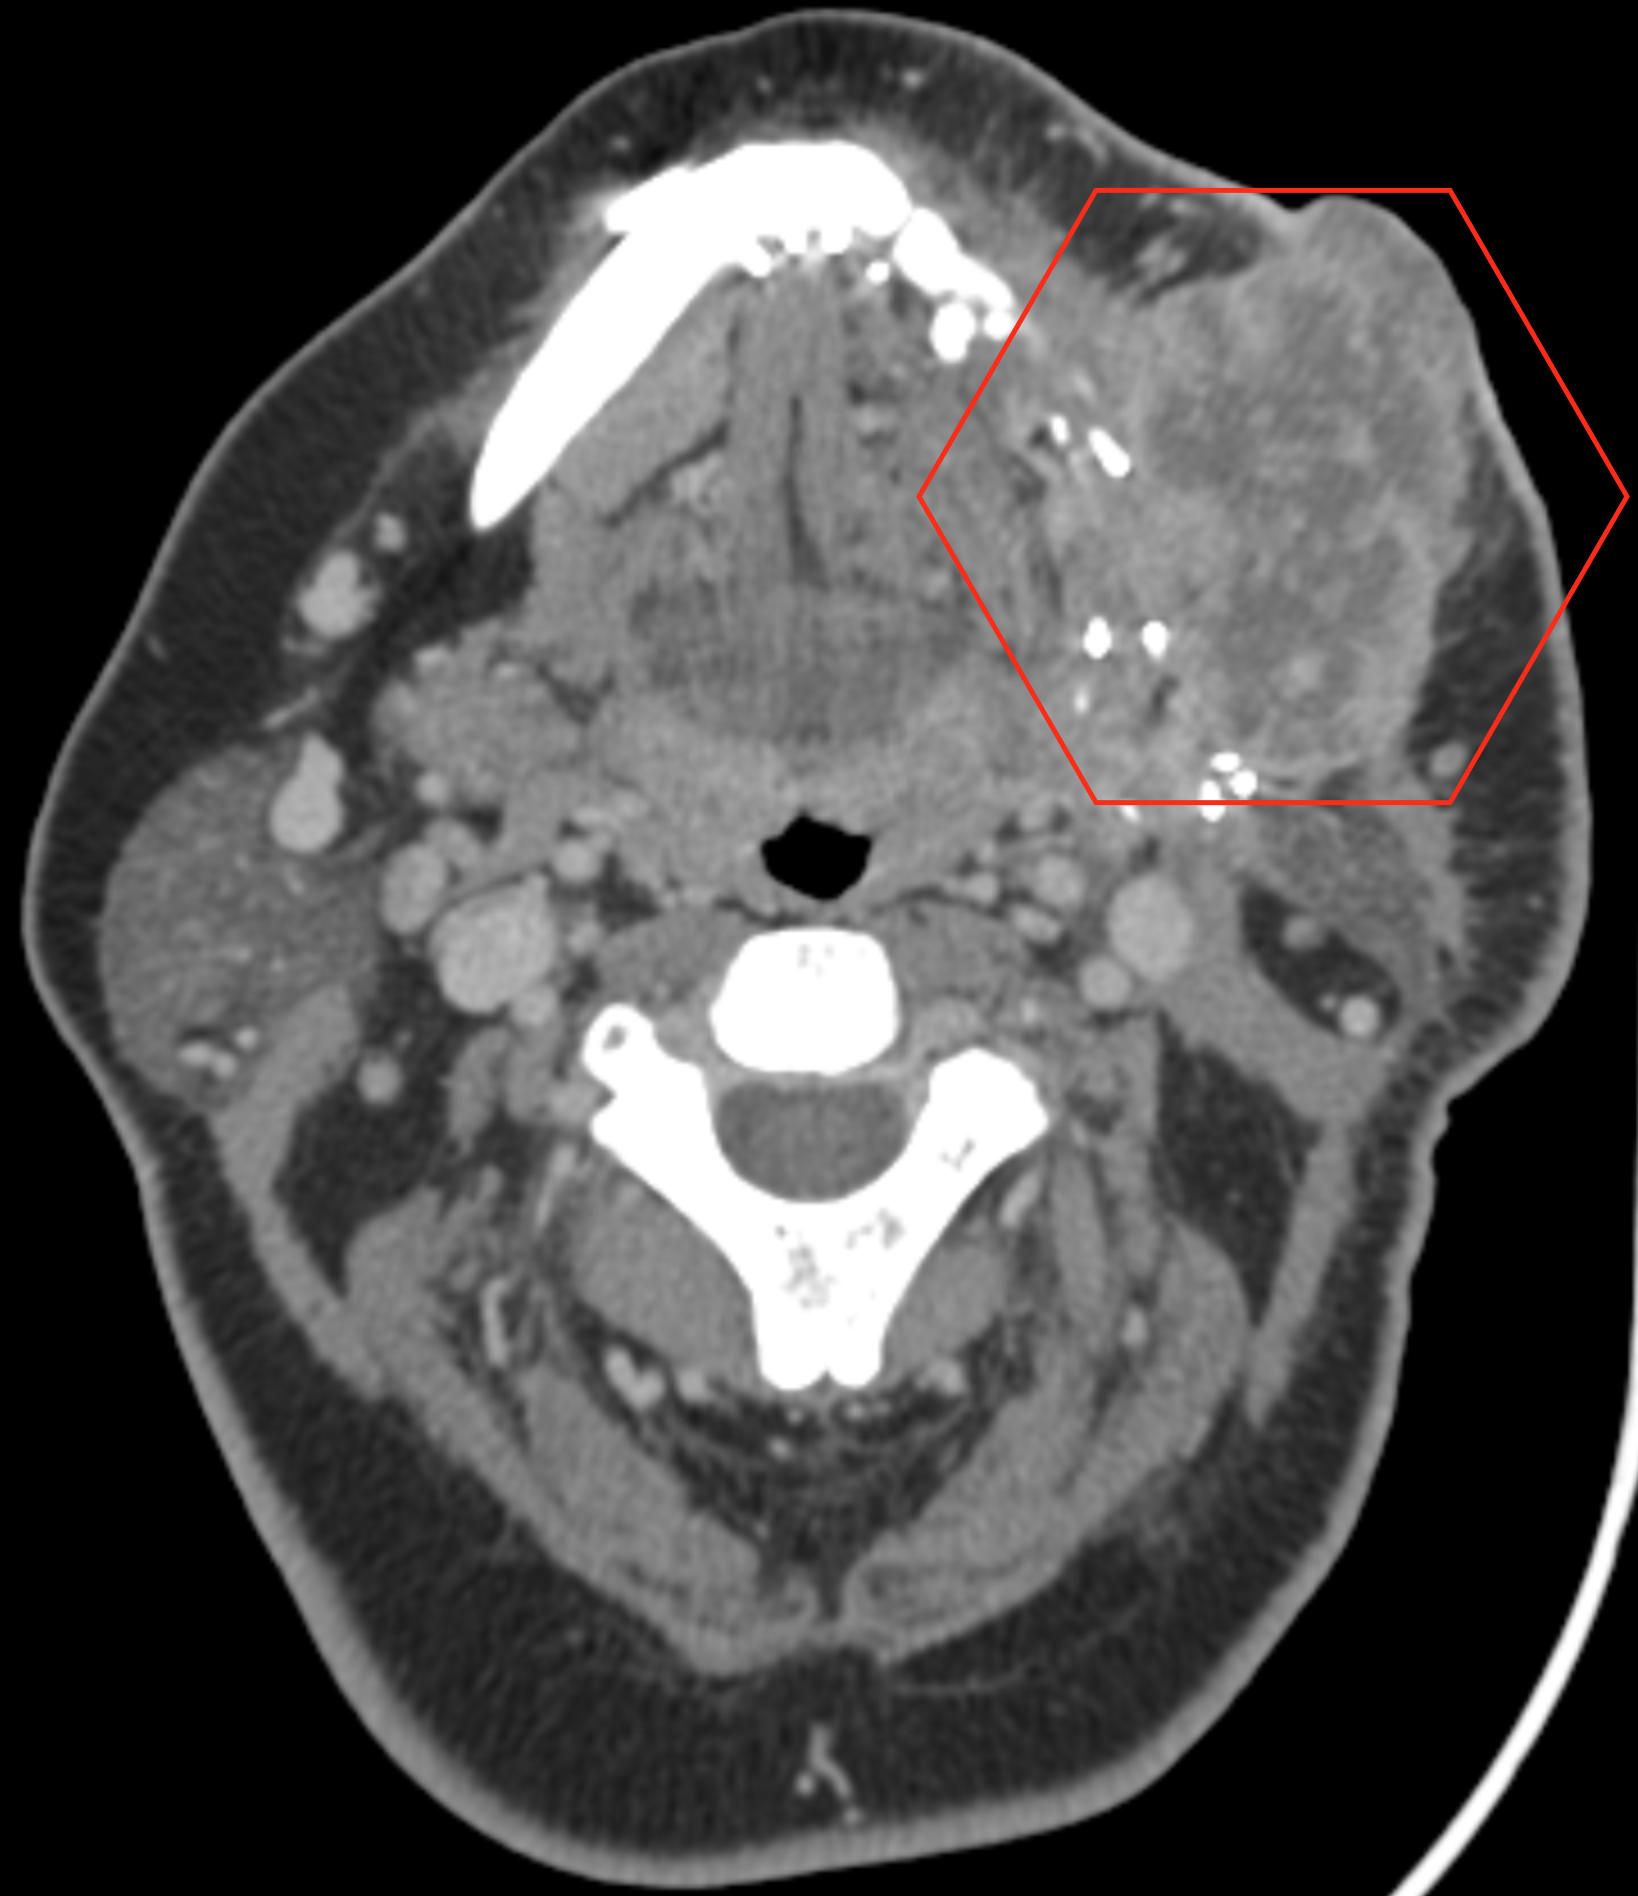

CT Scan

A computed tomography scan makes use of computer-processed combinations of many X-ray measurements taken from different angles to produce cross-sectional images of specific areas of a scanned object, allowing the user to see inside the object without cutting.

More CT Scans - February 10th 2020

Since Rob was here for a visit this week, we thought we would treat him to a day at MD Anderson downtown! Although we are not, by any means, out of the woods, we received some encouraging news. Christine had another CT scan today, and scan images (on web page), shows the tumor that was identified on December 19th, has considerably reduced in size after the two rounds of chemotherapy. Dr. Blumenschein was absolutely gobsmacked with these results. Christine will be having a third round of chemotherapy on Wednesday, after which the remaining tumor will be surgically removed on March 13th. We both thank you all very much for your continual support and good wishes. Christine will likely be out of action from Saturday for five or six days due to the fatigue caused by the chemotherapy treatment.